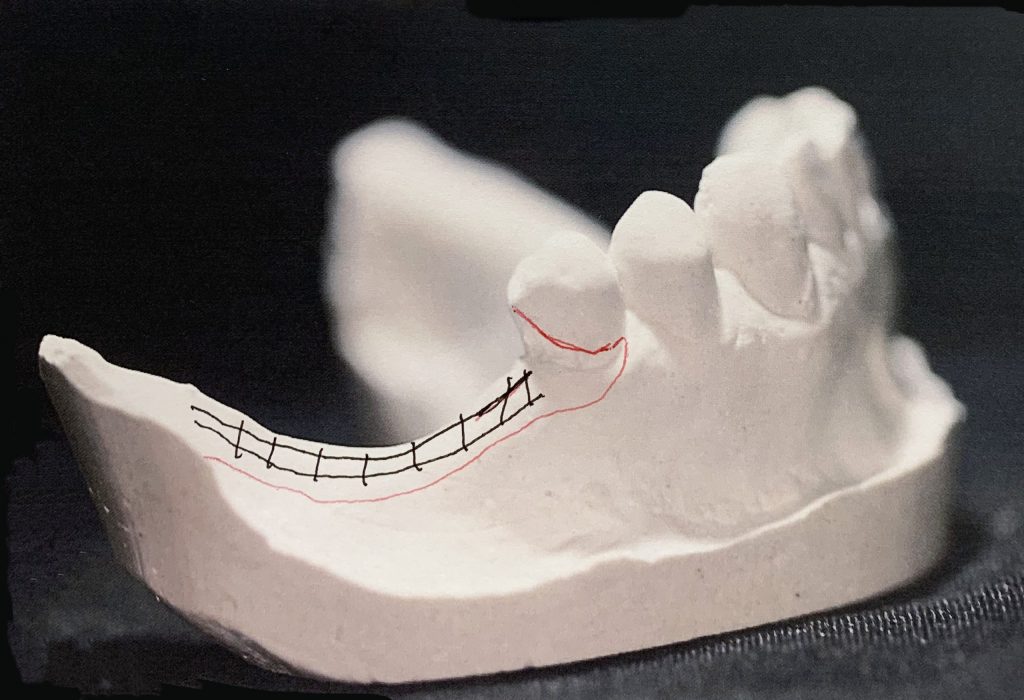

This case serves as an example of a Kennedy Class I

Kennedy Class I is a significantly challenging denture since it has a rotational fulcrum: Two flexible direct retention retainers are needed with the use of stress relief clasps that prevent torquing forces to the abutment.

Provision of indirect retention prevents the rotation of the denture.

Design & Blockout Example

Design for a case with long free end saddles.

The angulation of the teeth present a challenge with path of insertion.

Adding too much blockout could work against you in this case.